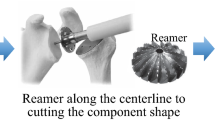

Surgical technique

All the procedures were performed in one centre, by two surgeons with significant experience level in shoulder arthroplasty (AJ, DM). Planning parameters and 3D views of the scapula, the implant, and the virtual guidewire were printed and displayed in the operating room (Fig. 2). For all the patients, the humeral implant was an ASCEND FLEX short uncemented stem (Tornier SAS, Montbonnot Saint Martin, France) and glenoid component was a PerFORM polyethylene keeled cemented component (Tornier SAS, Montbonnot Saint Martin, France). After residual cartilage removal, guidewire positioning and reaming were performed freehand, based on planning parameters and displayed 3D views, without any specific guide. Then, glenoid preparation was performed using a standard compacted autograft technique [23] and low viscosity cement.